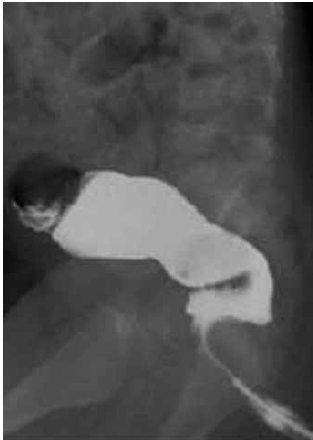

Recém-nascido a termo, sexo masculino, com 27 dias de vida, apresenta distensão abdominal desde o nascimento e vômitos há dois dias. A mãe do paciente relata que a primeira evacuação ocorreu aos três dias de vida e que, desde então, ele somente evacua após aplicação de supositório de glicerina, via retal, que vem sendo realizada a cada três dias, conforme orientação médica. Ao exame físico: irritado, pouco desidratado, abdome distendido, sem reação peritoneal. Toque retal com eliminação de fezes explosivas em grande quantidade. Após realização de lavagem intestinal com solução fisiológica, houve saída de grande quantidade de fezes e relevante melhora da distensão abdominal. O paciente realizou enema opaco, conforme imagem a seguir:

O próximo passo na condução desse caso deve ser